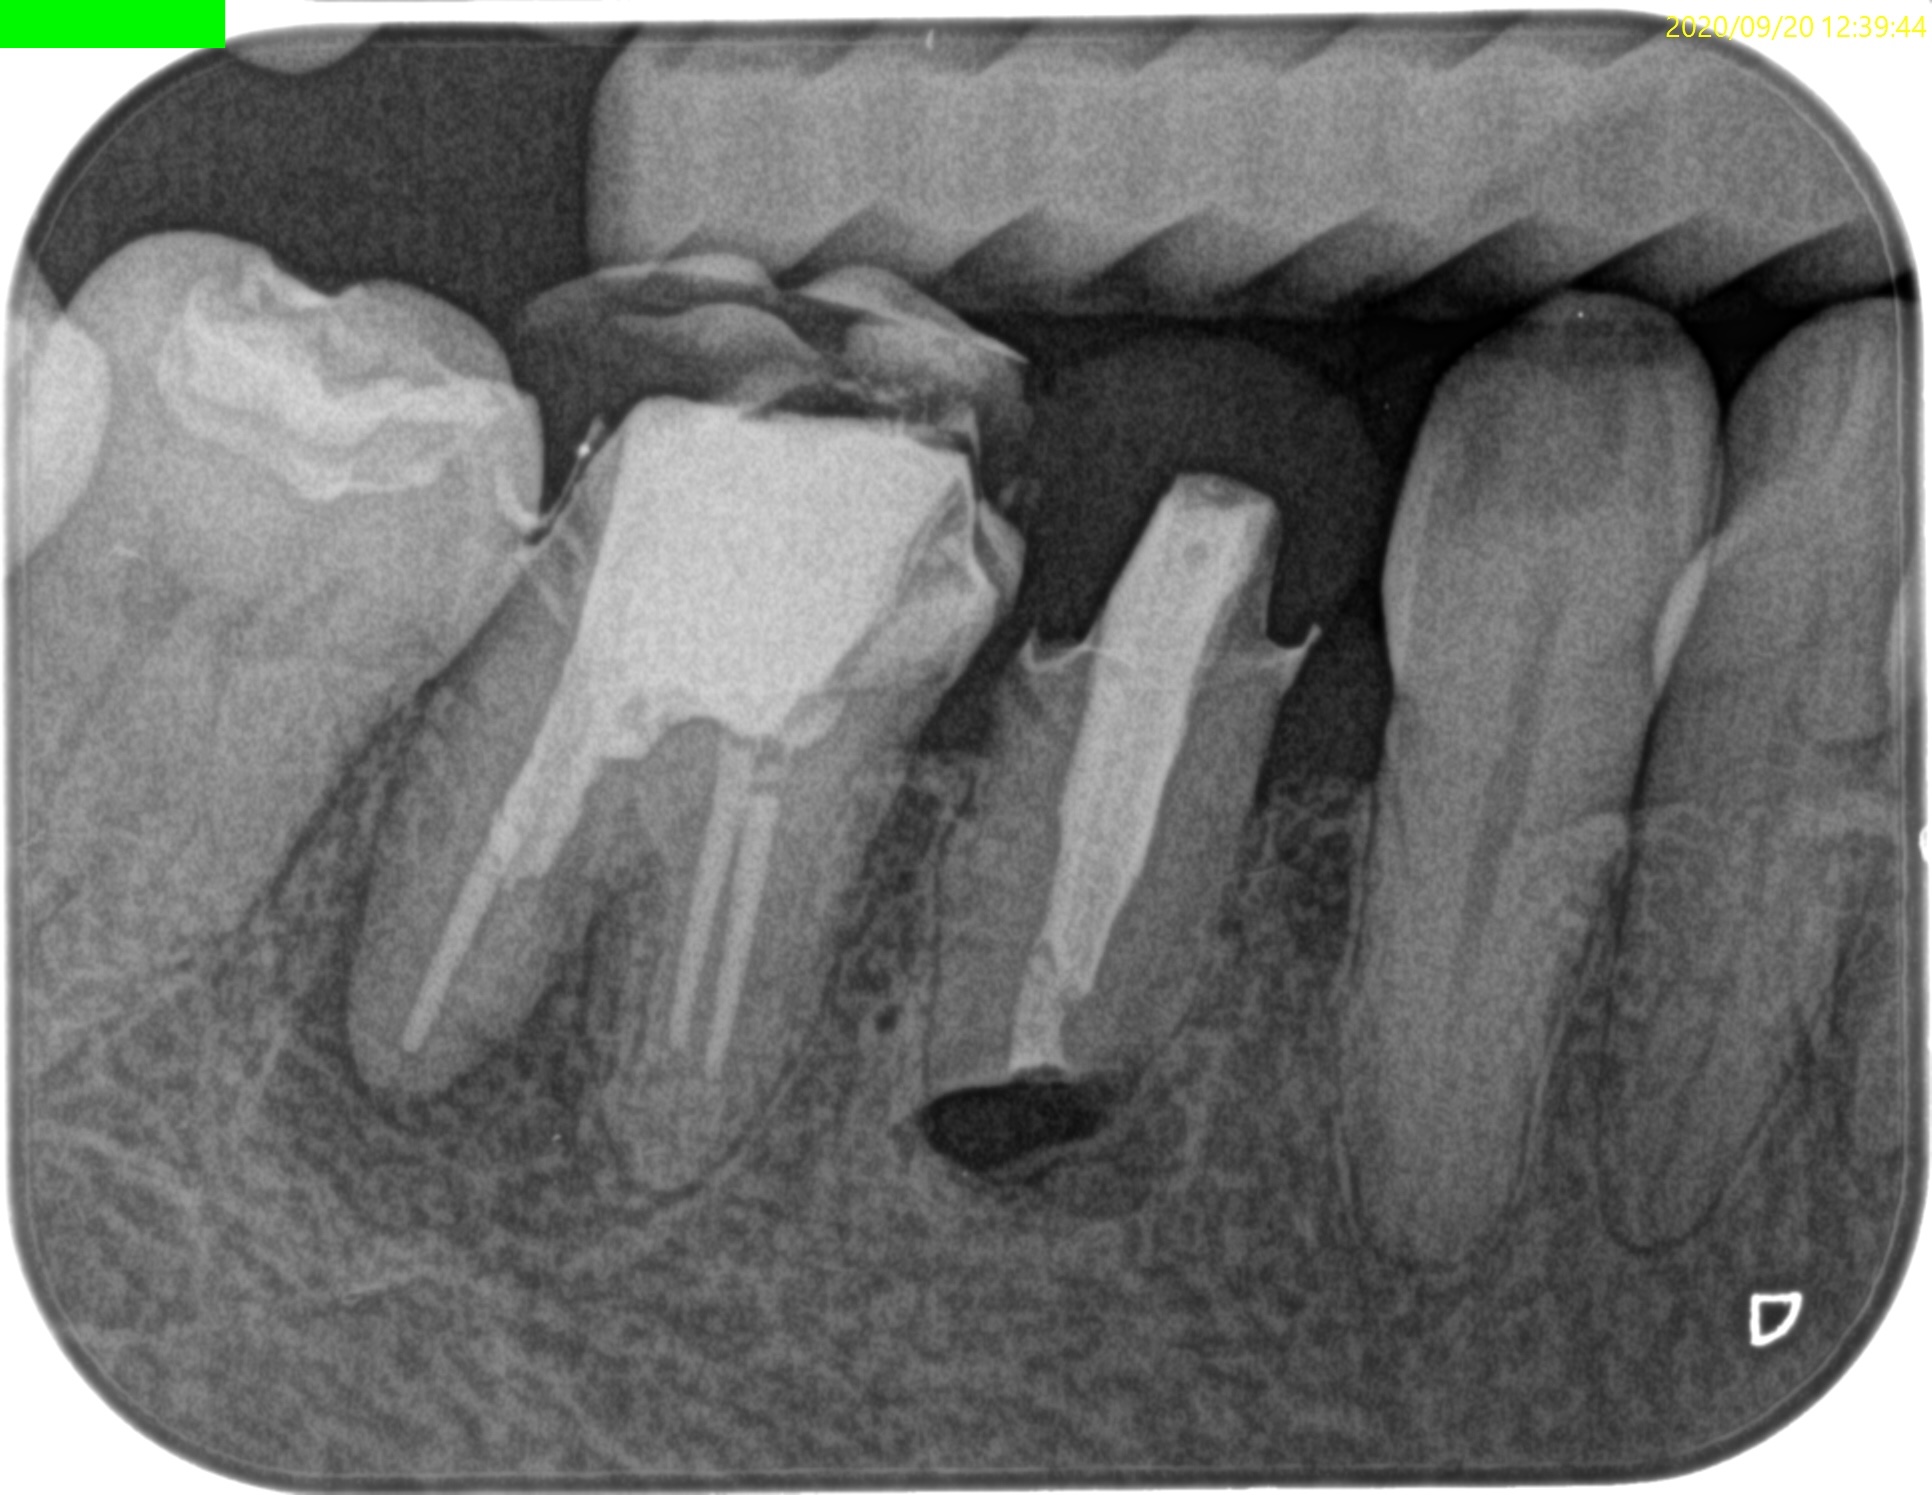

時系列は以下だ。2020.9.20に#29 Apicoectomyをしている。